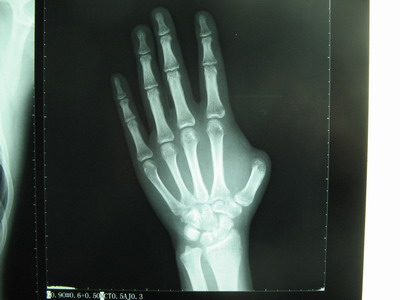

术前拍片

日前,我院手外科主任、学科带头人马志鹏主任为患者陈某实施足趾移植再造左手拇指获得成功,术后,该“拇指”能屈能伸,外观、功能恢复理想。据了解,这是我院成功用足趾移植再造的第25例手术,表明我院显微手外科技术居省内先进水平。 伤者小陈于2月前不慎被机器压伤致“左拇五度缺损”,这意味着左手从此失去了大拇指,且丧失40%的功能。当时做了残修术的小陈了解到我院再造手术开展得不错时,回院强烈要求为其行“左拇再造术”。3月5日,在马主任的指挥领导下,历时十多个小时,用小陈的右足趾移植再造其左手大拇指获得成功。 术后,小陈在医院医护人员的精心治疗和护理下,顺利度过了血管痉挛和感染期,伤口愈合良好,再造的大拇指可以伸展活动。马主任介绍说,经过一段时间的锻炼,再造拇指的外形和功能还将进一步得到恢复。 |